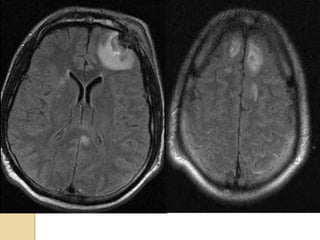

Axial FLAIR imagesAxial FLAIR images

AXIAL FLAIRAXIAL FLAIR